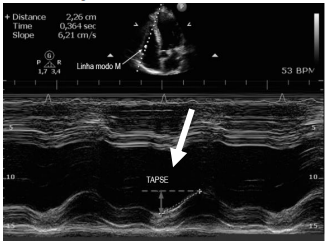

Os valores de TAPSE de =1.9cm (nl>1,6cm) onda S 13(nl>

10), indicam:

Observe a imagem abaixo:

A seta na imagem indica TAPSE que consiste: